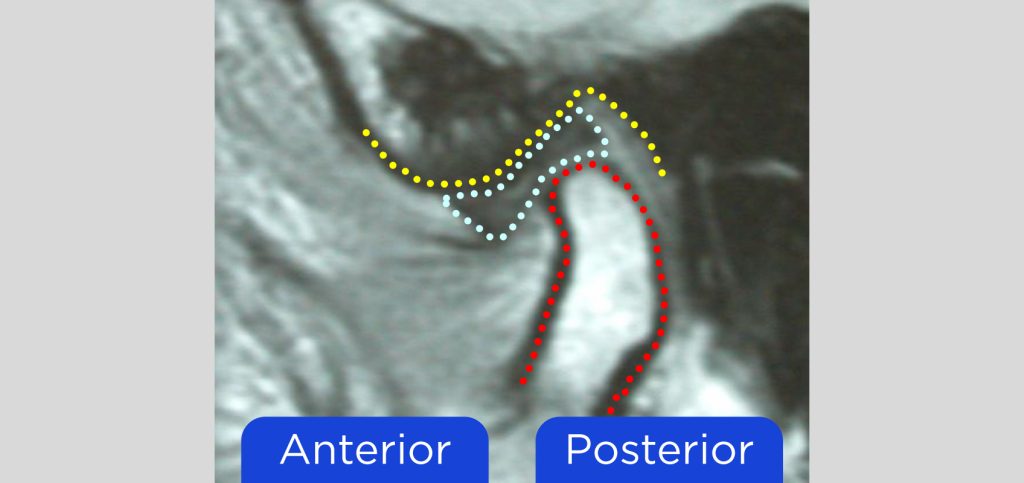

That factor is an intact condyle–disc assembly. If the disc is displaced, it’s not possible to have “normal joints fitting in normal joint sockets.” It may be more detrimental to use a superior condylar position in the type of patient seen in Fig. 2, for example, because there is no soft-tissue protection at the joint level.